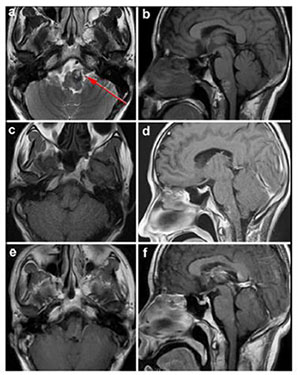

MRI is the most necessary examination for BSCMs in terms of diagnosis and differential diagnosis. CTA and DSA play important roles in distinguishing CMs with AVMs. Because of hemorrhage, typical imaging appearances of BSCMs are hyperintense core (methemoglobin) surrounded by hypointense rim (hemosiderin) on both T1-and T2-weighted MRI (Figure 1). Gradient-echo scan, especially susceptibility weighted imaging (SWI), can be used to find small occult lesions. CTA or DSA generally failed to reveal the BSCMs because of lacking feeding arteries.

| Figure 1 MRI demonstrated the typical "porpcorn" or "mulberry-like" BSCMs. (a), (b) and (c) showed one patient with pontine cavernoma. (d), (e) and (f) showed another patient with left cerebellar peduncle cavernoma. (a) and (d) axial T1-weighted, (b) and (e) axial T2-weighted, (c) axial enhanced T1-weighted, (f) SWI. |